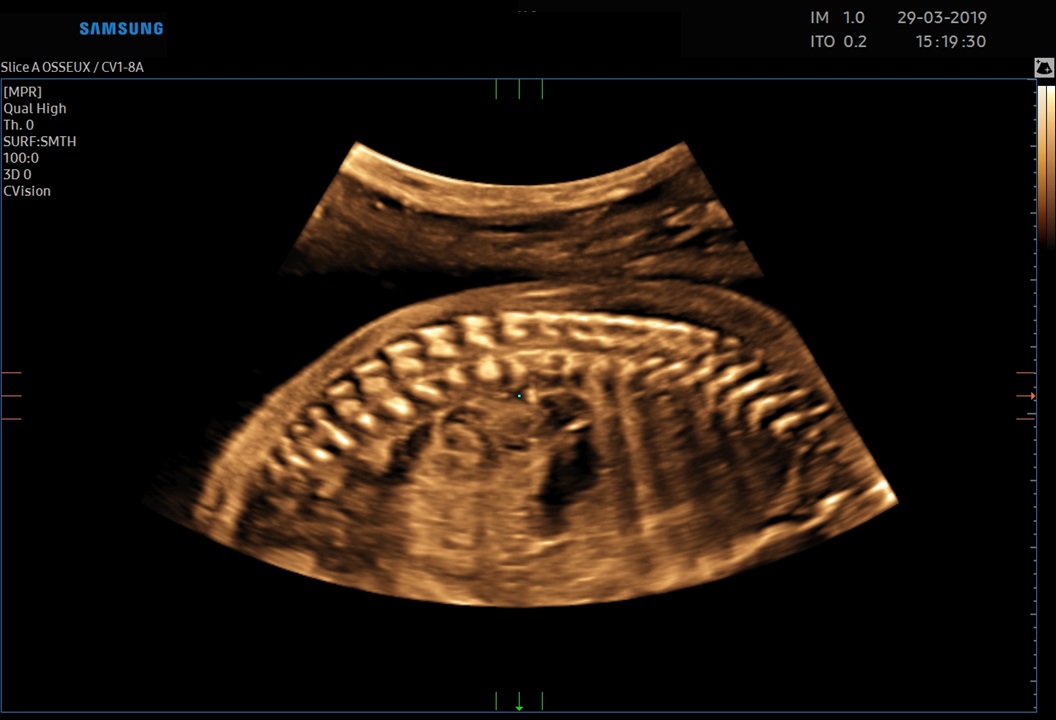

Les sondes de technologie S-Vue™ disposent d'une sensibilité accrue et d'une bande passante plus large que les sondes conventionnelles. Elles garantissent une résolution d’image optimale, même chez les patientes techniquement difficiles. De plus la petite taille et la légèreté de ces sondes améliorent les conditions d'examen au quotidien.

Obstétrique, gynécologie, abdomen, pédiatrie